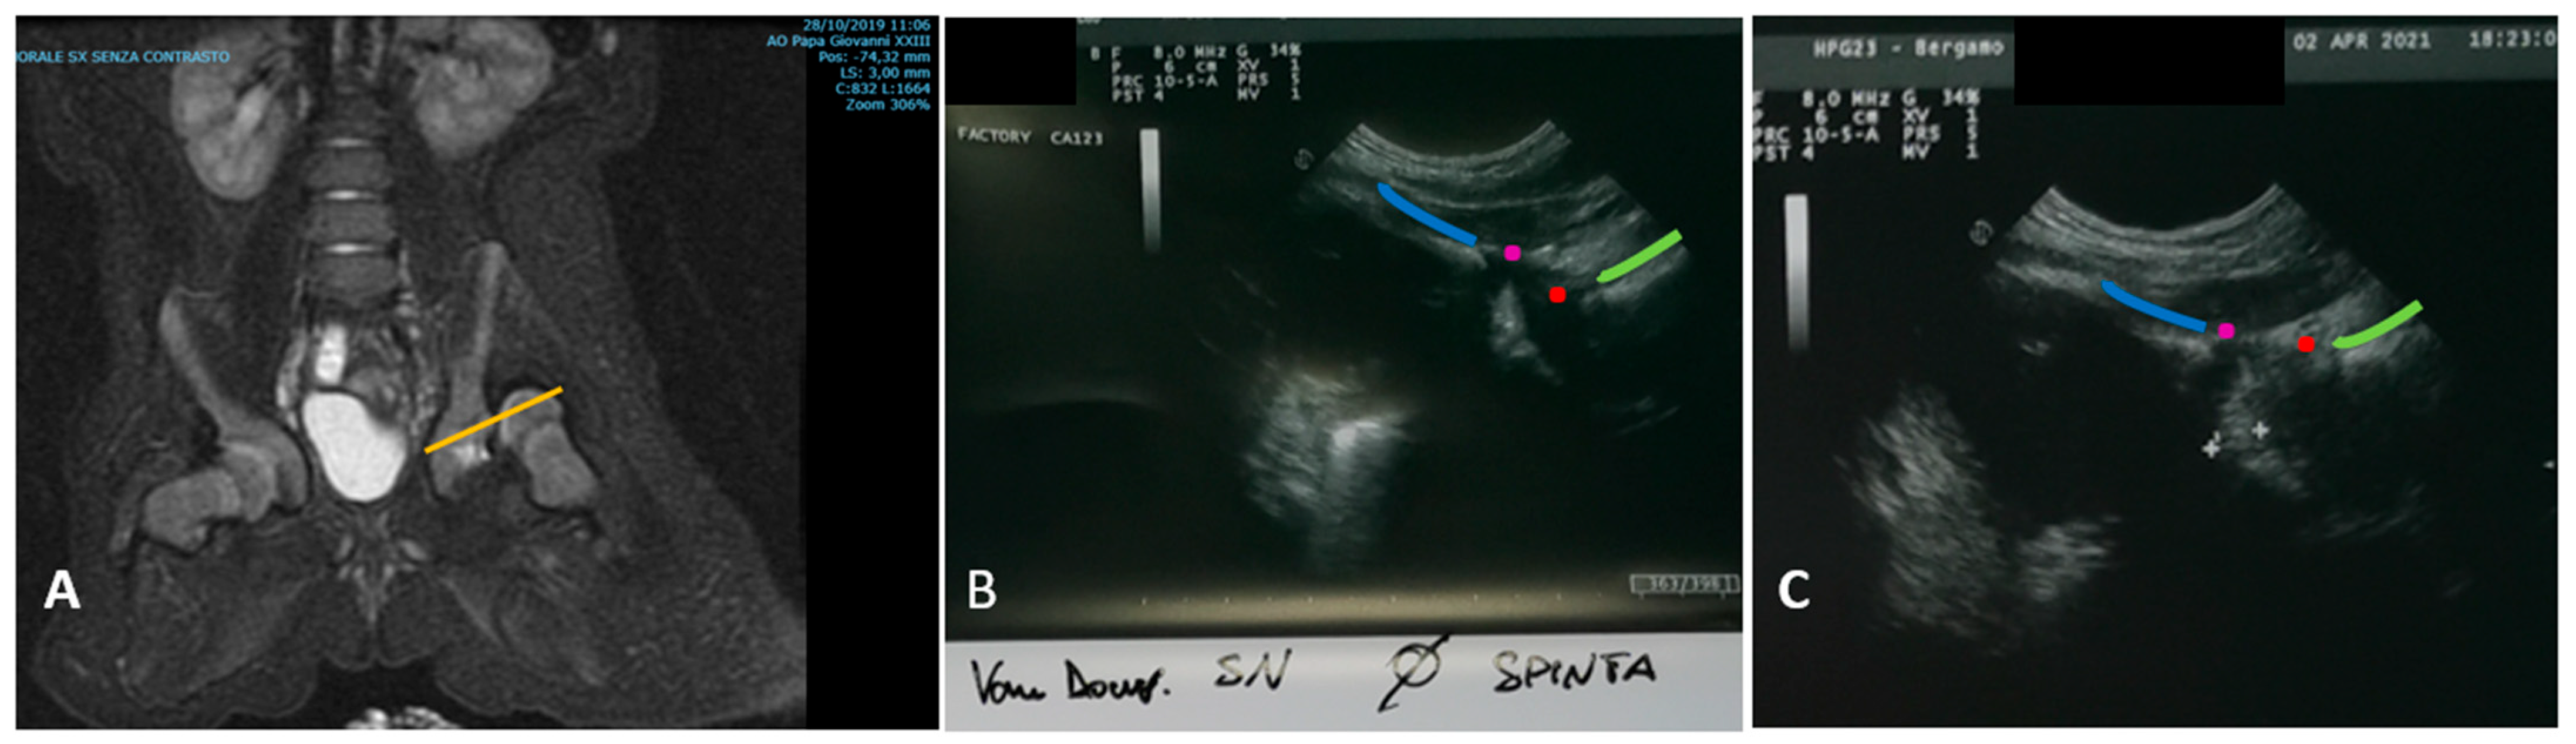

- Eberhardt, O.; Zieger, M.; Wirth, T.; Fernandez, F.F. Determination of femoral head position with transinguinal ultrasound in DDH treatment. Z. Orthop. Unfall. 2009, 147, 727–733. [Google Scholar] [CrossRef] [PubMed]

- van Douveren, F.Q.M.P.; Pruijs, H.E.H.; Sakkers, R.J.B.; Nievelstein, R.A.J.; Beek, F.J.A. Ultrasound in the management of the position of the femoral head during treatment in a spica cast after reduction of hip dislocation in developmental dysplasia of the hip. J. Bone Jt. Surg. Ser. B 2003, 85, 117–120. [Google Scholar] [CrossRef]

- Beek, F.J.A.; Nievelstein, R.J.; Pruijs, H.E.; De Jong, P.A.; Sakkers, R.J.B. Transinguinal sonographic determination of the position of the femoral head after reposition and follow-up in a spica cast. Pediatr. Radiol. 2010, 40, 1794–1799. [Google Scholar] [CrossRef] [PubMed]